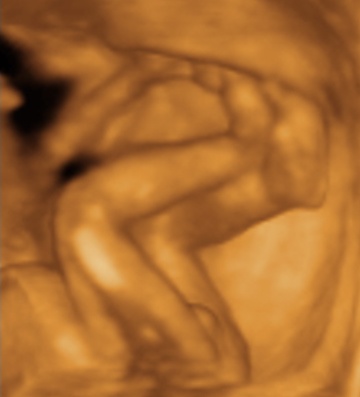

Szép kálvária volt a doki, de örülök, hogy minden rendben! Nagyon szépek a képek, tök formás már ilyen idősen. Az én kiscsajomnak ugyanebben a korban sokkal vékonyabb arca volt, de akkor ezek szt rám ütött, mert nekem is vékony az arcom.